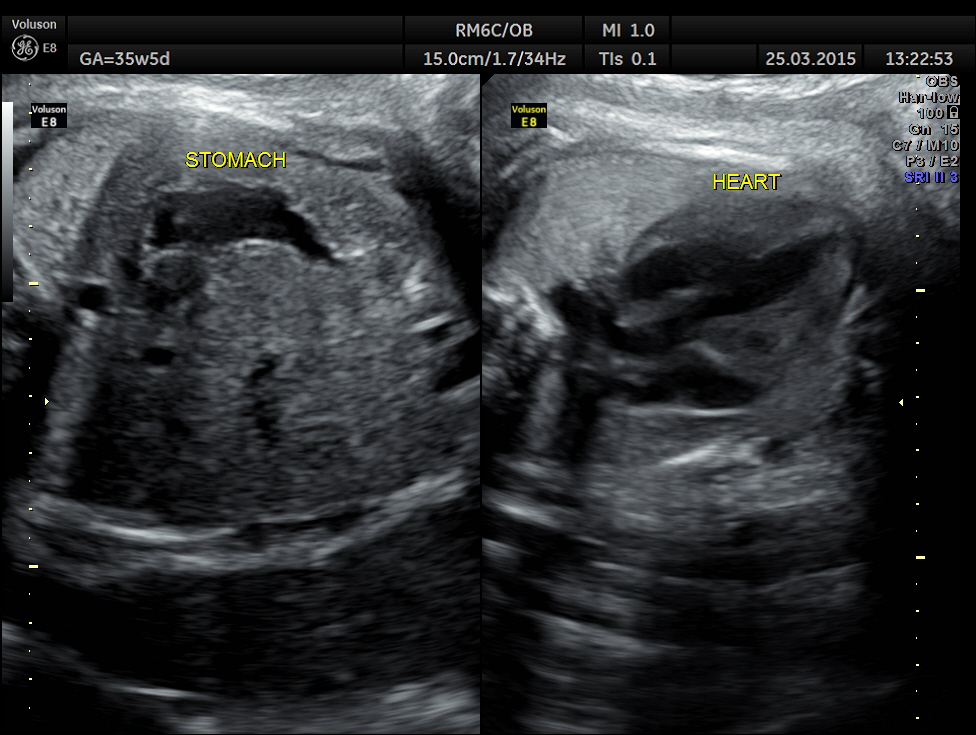

The following picture shows a normal situs and axis . The great vessels running parallel are also seen.

The 4 chamber view showed LV to be dilated.